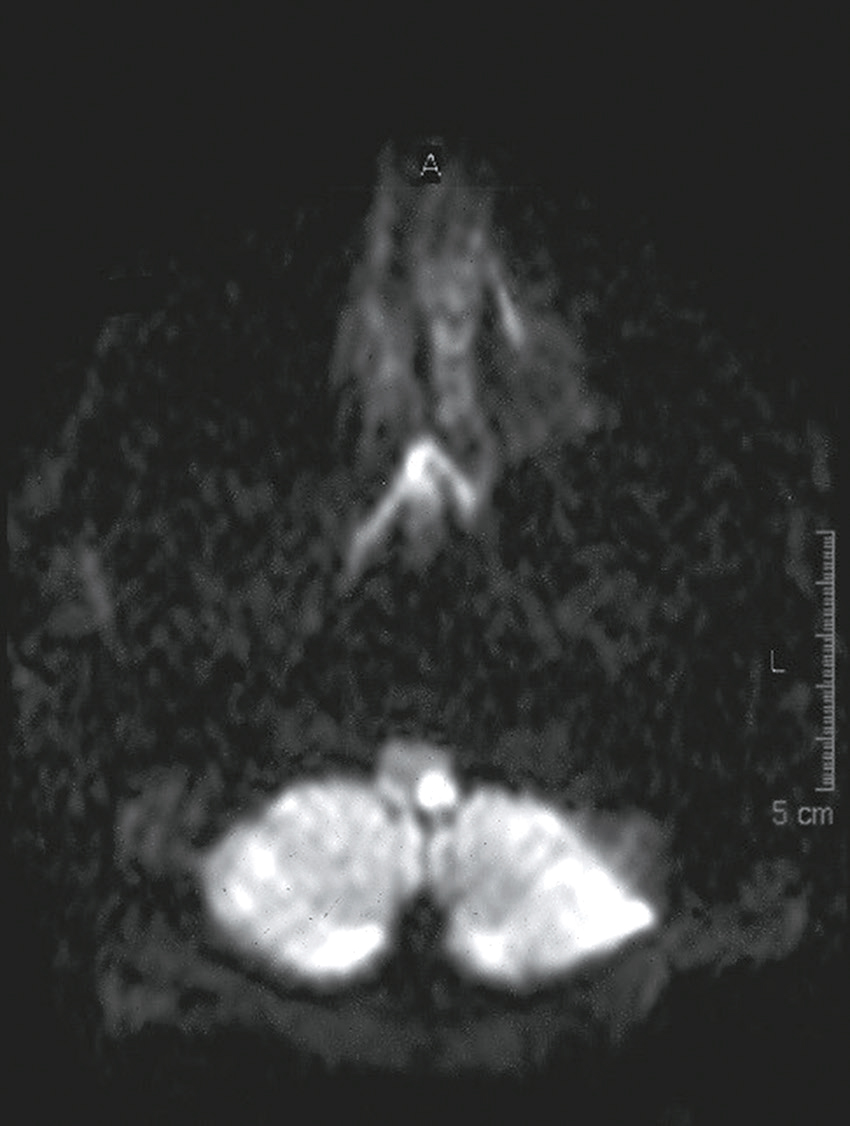

Vous débutez un traitement par benzodiazépine, vitaminothérapie B1, B6, PP, réhydratation par sérum salé et immunoglobulines polyvalentes intraveineuses associées à une héparine de bas poids moléculaire à dose isocoagulante. Le lendemain matin, le patient s’est aggravé d’un point de vue clinique. Il n’a plus d’hallucination visuelle mais il présente maintenant une tétraparésie évaluée à 3/5 avec ataxie des quatre membres, une dysarthrie, des troubles de la déglutition, et une ophtalmoplégie bilatérale. Un bilan biologique a été prélevé avant votre arrivée : numération formule sanguine : Hb : 13,8 g/dL, leucocytes : 8 600/ mm3, plaquettes : 332 000/mm3, ionogramme sanguin : Na+ : 142 mmol/L, K+ : 4,2 mmol/L, clairance de la créatininémie : 92 mL/min, glycémie : 5,8 mmol/L, transaminases, phosphatases alcalines, bilirubines et γ-GT normales, CRP : 3 mg/L.

Une IRM cérébrale a été également réalisée (fig. 31.4). Quelle est la séquence présentée ?

L'image montre une IRM (Imagerie par Résonance Magnétique) du cerveau humain en coupe axiale, c'est-à-dire une vue transversale du cerveau prise horizontalement. Cette image est particulièrement intéressante car elle permet de visualiser les structures internes du cerveau avec une grande précision. On peut observer les globes oculaires en haut de l'image, qui apparaissent comme deux cercles blancs. Les différentes zones du cerveau sont visibles, avec des variations de teintes qui indiquent les différentes densités des tissus cérébraux. La région centrale lumineuse correspond au tronc cérébral, une structure cruciale pour de nombreuses fonctions vitales. Les zones plus sombres autour du tronc cérébral représentent les hémisphères cérébraux. Cette image est utilisée pour diagnostiquer et évaluer diverses conditions neurologiques, telles que les tumeurs, les accidents vasculaires cérébraux, les infections, et les anomalies structurelles. L'IRM est une technique non invasive qui utilise des champs magnétiques et des ondes radio pour produire des images détaillées des organes et des tissus internes.

- A T1

- B écho de gradient

- C T2

- D T2/FLAIR

- E diffusion